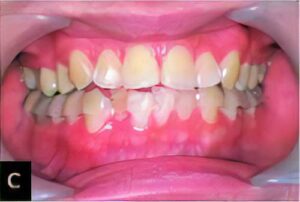

矯正治療時の抜歯

矯正治療で、歯並びを整えるため抜歯が必要な場合があります。その際、周囲の歯牙を傷つけず抜歯する、歯の根を折らないなどの配慮が必要です。